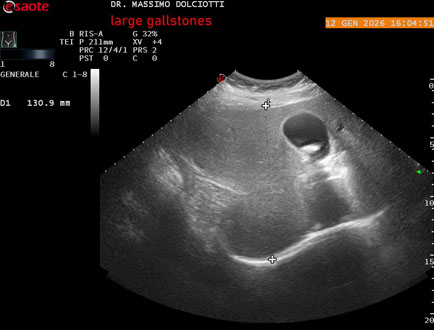

Data inserimento: 19/05/2025

Ecografia del: 30/04/2025

Strumento: Esaote MyLab Eight

Sonda: Convex Multifrequenza 1-8 MHz

Età Paziente: F 28 anni

Motivazione dell'esame: dolori addominali e vomito

Commento all'esame: le immagini ed il video documentano all'interno della colecisti, immagine iperecogena, con cono d'ombra posteriore, delle dimensioni di 21 mm, da ricondurre a litiasi.

Conclusioni: grosso calcolo della colecisti (large gallstone).

Presentazione: Dr. Massimo Dolciotti - Ancona

Elaborazione digitale: Andrea Dini - Ancona